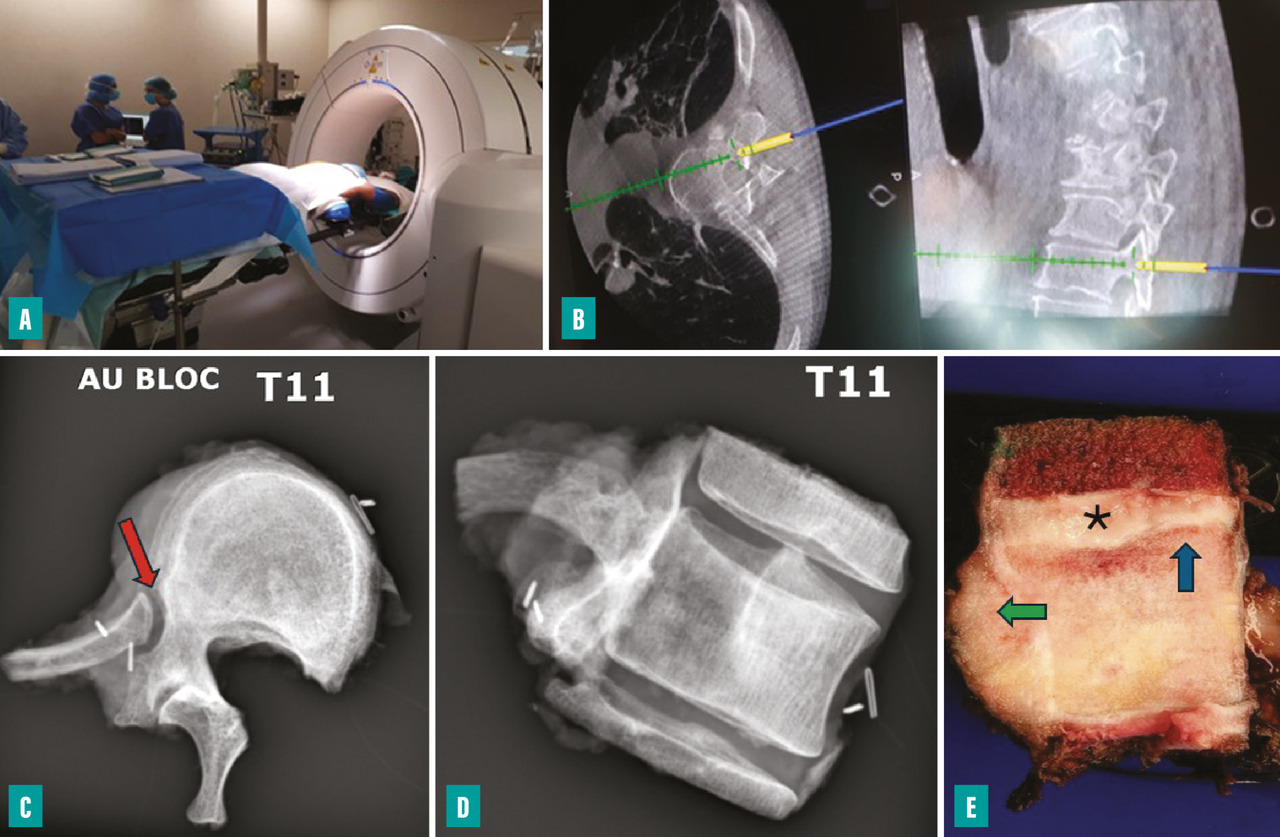

La résection d’un sarcome du rachis est une technique exigeante qui requiert généralement une prise en charge multidisciplinaire (thoracique, vasculaire, orthopédique). Les vertébrectomies totales en bloc sont préférentiellement réalisées par des voies d’abord combinées afin de sécuriser la qualité des marges et de limiter le risque de choc hémorragique.5,6

Les séquences opératoires peuvent être résumées en quatre étapes :

• libération postérieure par une voie verticale médiane standard (laminectomie des étages adjacents et préparation d’un passage pour la moelle, en fonction de l’extension tumorale dans l’arc postérieur) et fixation par la même voie postérieure ;

• libération antérieure (à ciel ouvert ou vidéo-assistée) ;

• vertébrectomie proprement dite (habituellement réalisée par la voie postérieure) ;

• reconstruction vertébrale antérieure par cage, plus ou moins ostéosynthèse lorsqu’elle est requise.

L’utilisation d’un système de navigation peropératoire (scanner peropératoire ou guides de coupe) permet de contrôler le trajet de l’ostéotomie (fig. 4). La libération de la moelle n’est possible que si au moins un des deux pédicules (voire une lame) est intact. Pour le rachis cervical, l’exposition lors de la libération antérieure est essentiellement limitée par les rapports avec les artères carotides externes et les artères vertébrales. Une interruption du flux artériel est parfois rendue nécessaire afin de limiter le saignement peropératoire (ligature de la carotide externe ou occlusion endovasculaire de la vertébrale).